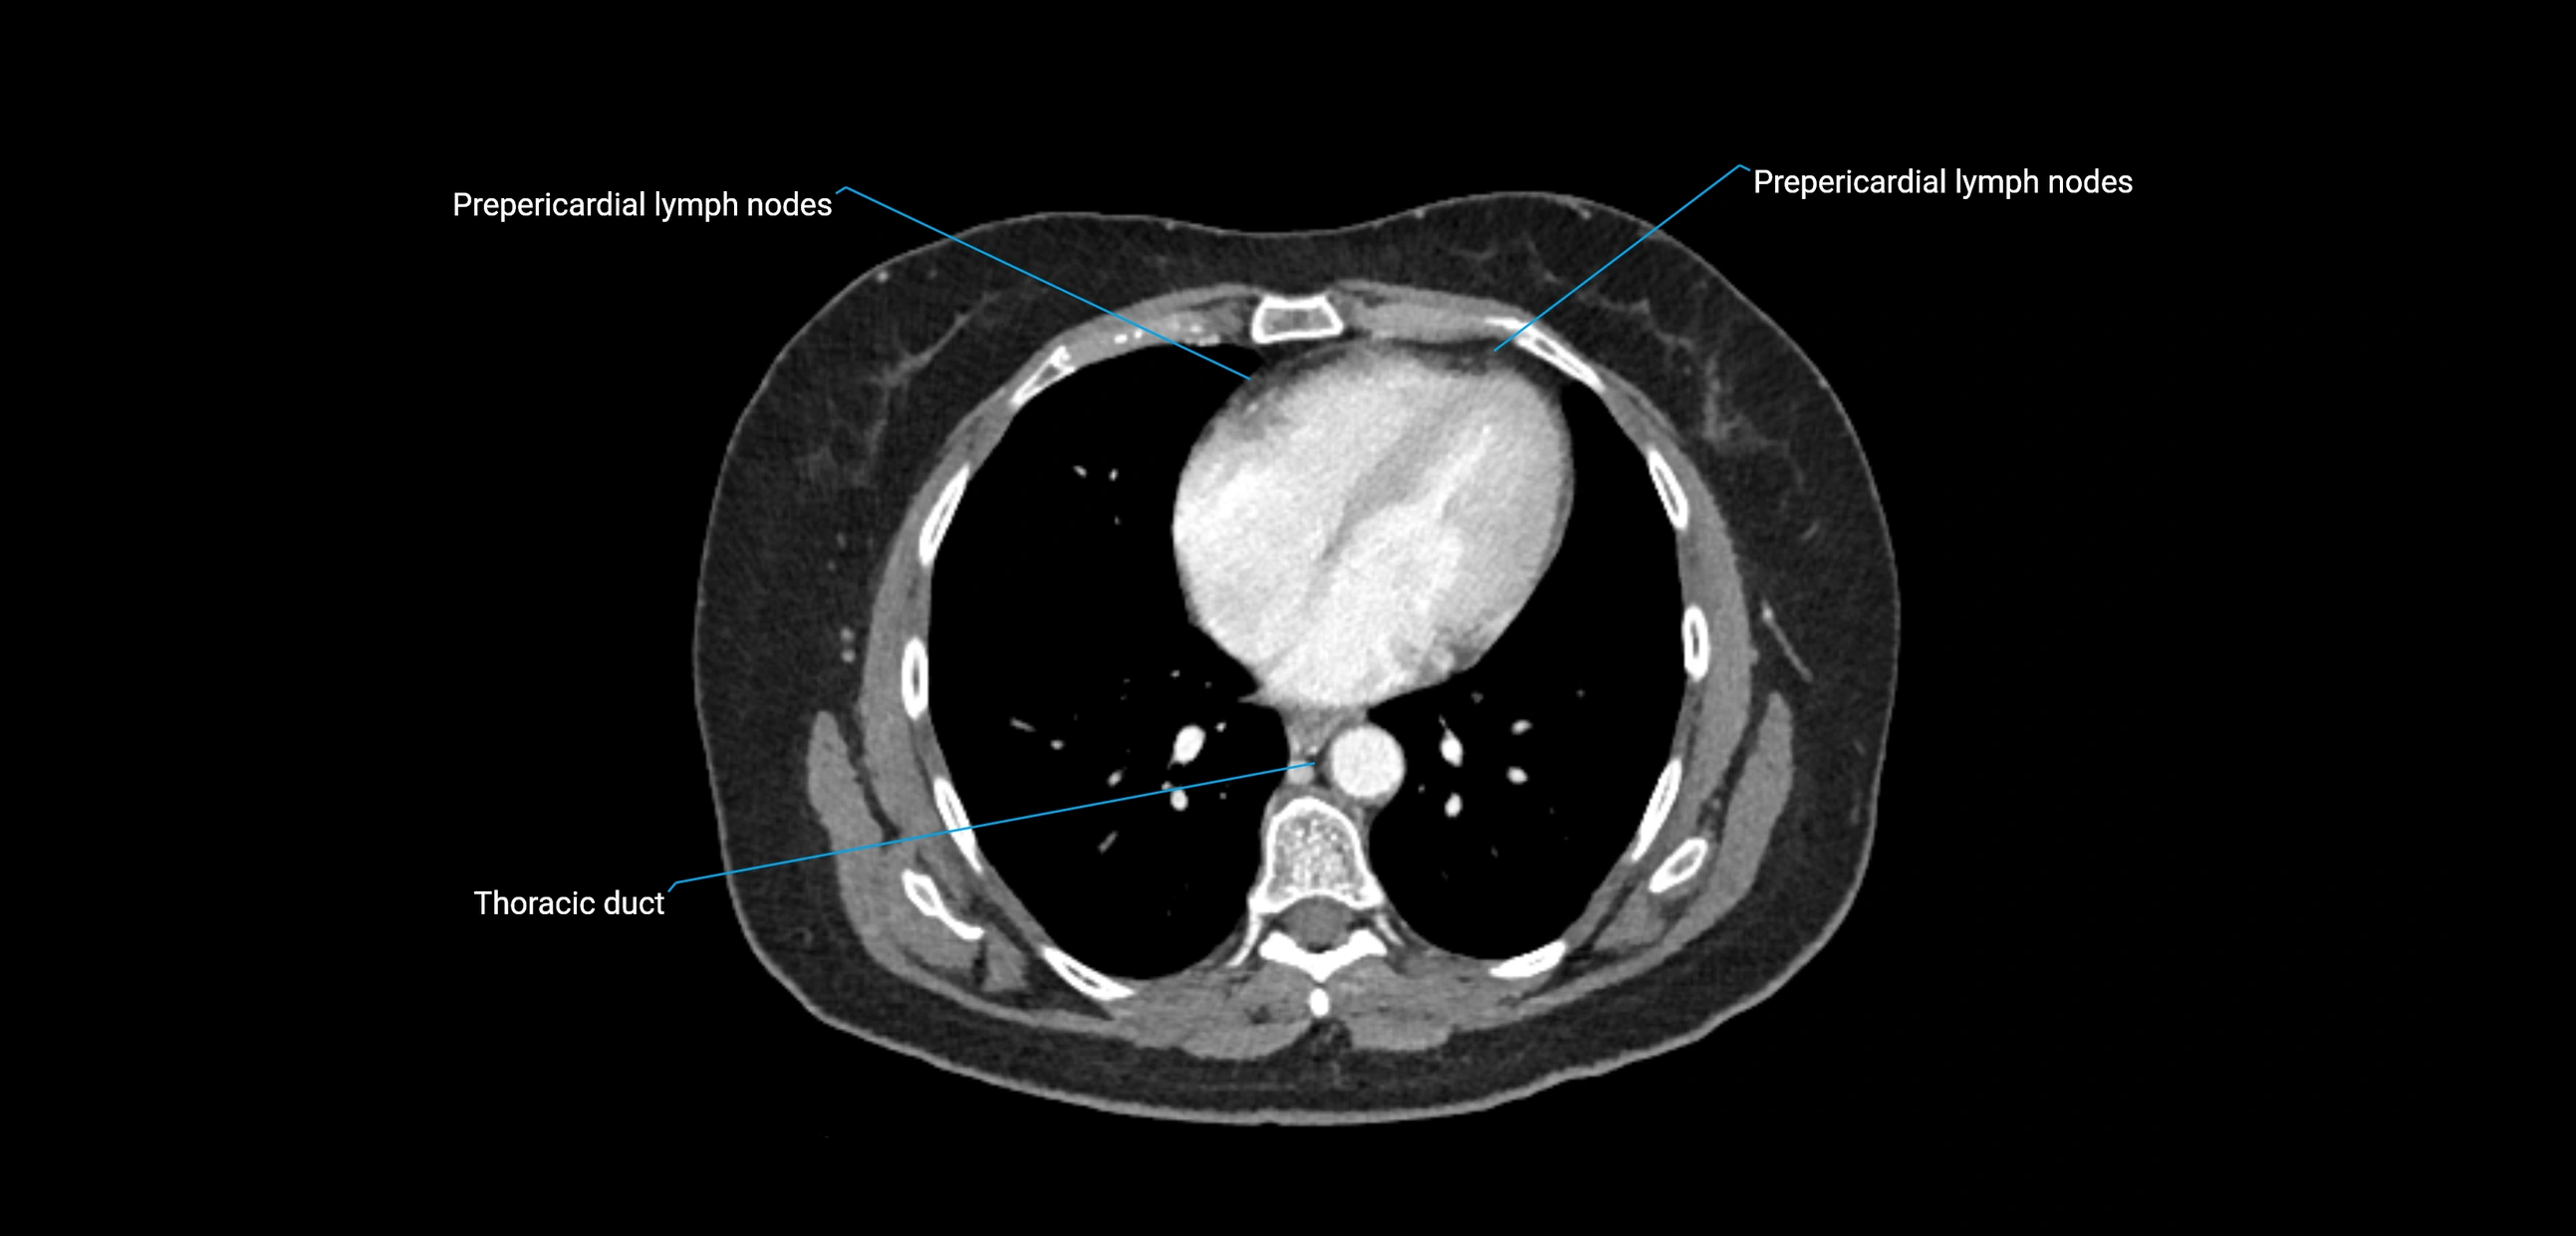

CT Appearance

CT Post-Contrast:

• Normal nodes enhance homogeneously

• Malignant nodes may show heterogeneous enhancement, central necrosis, or conglomerate formation

CT Venography (CTV):

• Demonstrates nodal encasement or compression of adjacent vessels (aorta, IVC, renal veins)

• Useful in staging testicular and ovarian malignancies

• Provides 3D reconstructions for retroperitoneal lymph node dissection planning